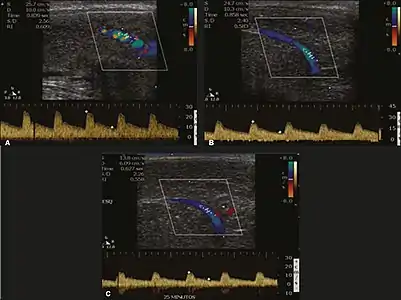

Before the injection of the chosen drug, the flow pattern is monophasic, with low systolic velocities and an absence of diastolic flow. After injection, systolic and diastolic peak velocities should increase, decreasing progressively with vein occlusion and becoming negative when the penis becomes rigid (see image below). The reference values vary across studies, ranging from > 25 cm/s to > 35 cm/s. Values above 35 cm/s indicate the absence of arterial disease, values below 25 cm/s indicate arterial insufficiency, and values of 25–35 cm/s are indeterminate because they are less specific (see image below). The data obtained should be correlated with the degree of erection observed. If the peak systolic velocities are normal, the final diastolic velocities should be evaluated, those above 5 cm/s being associated with venogenic ED.[44]

Graphs representing the color Doppler spectrum of the flow pattern of the cavernous arteries during the erection phases. A: Single-phase flow with minimal or absent diastole when the penis is flaccid. B: Increased systolic flow and reverse diastole 25 min after injection of prostaglandin.[44]

Longitudinal, ventral ultrasound of the penis, with pulsed mode and color Doppler. Flow of the cavernous arteries at 5, 15, and 25 min after prostaglandin injection (A, B, and C, respectively). The cavernous artery flow remains below the expected levels (at least 25–35 cm/s), which indicates ED due to arterial insufficiency.[44]